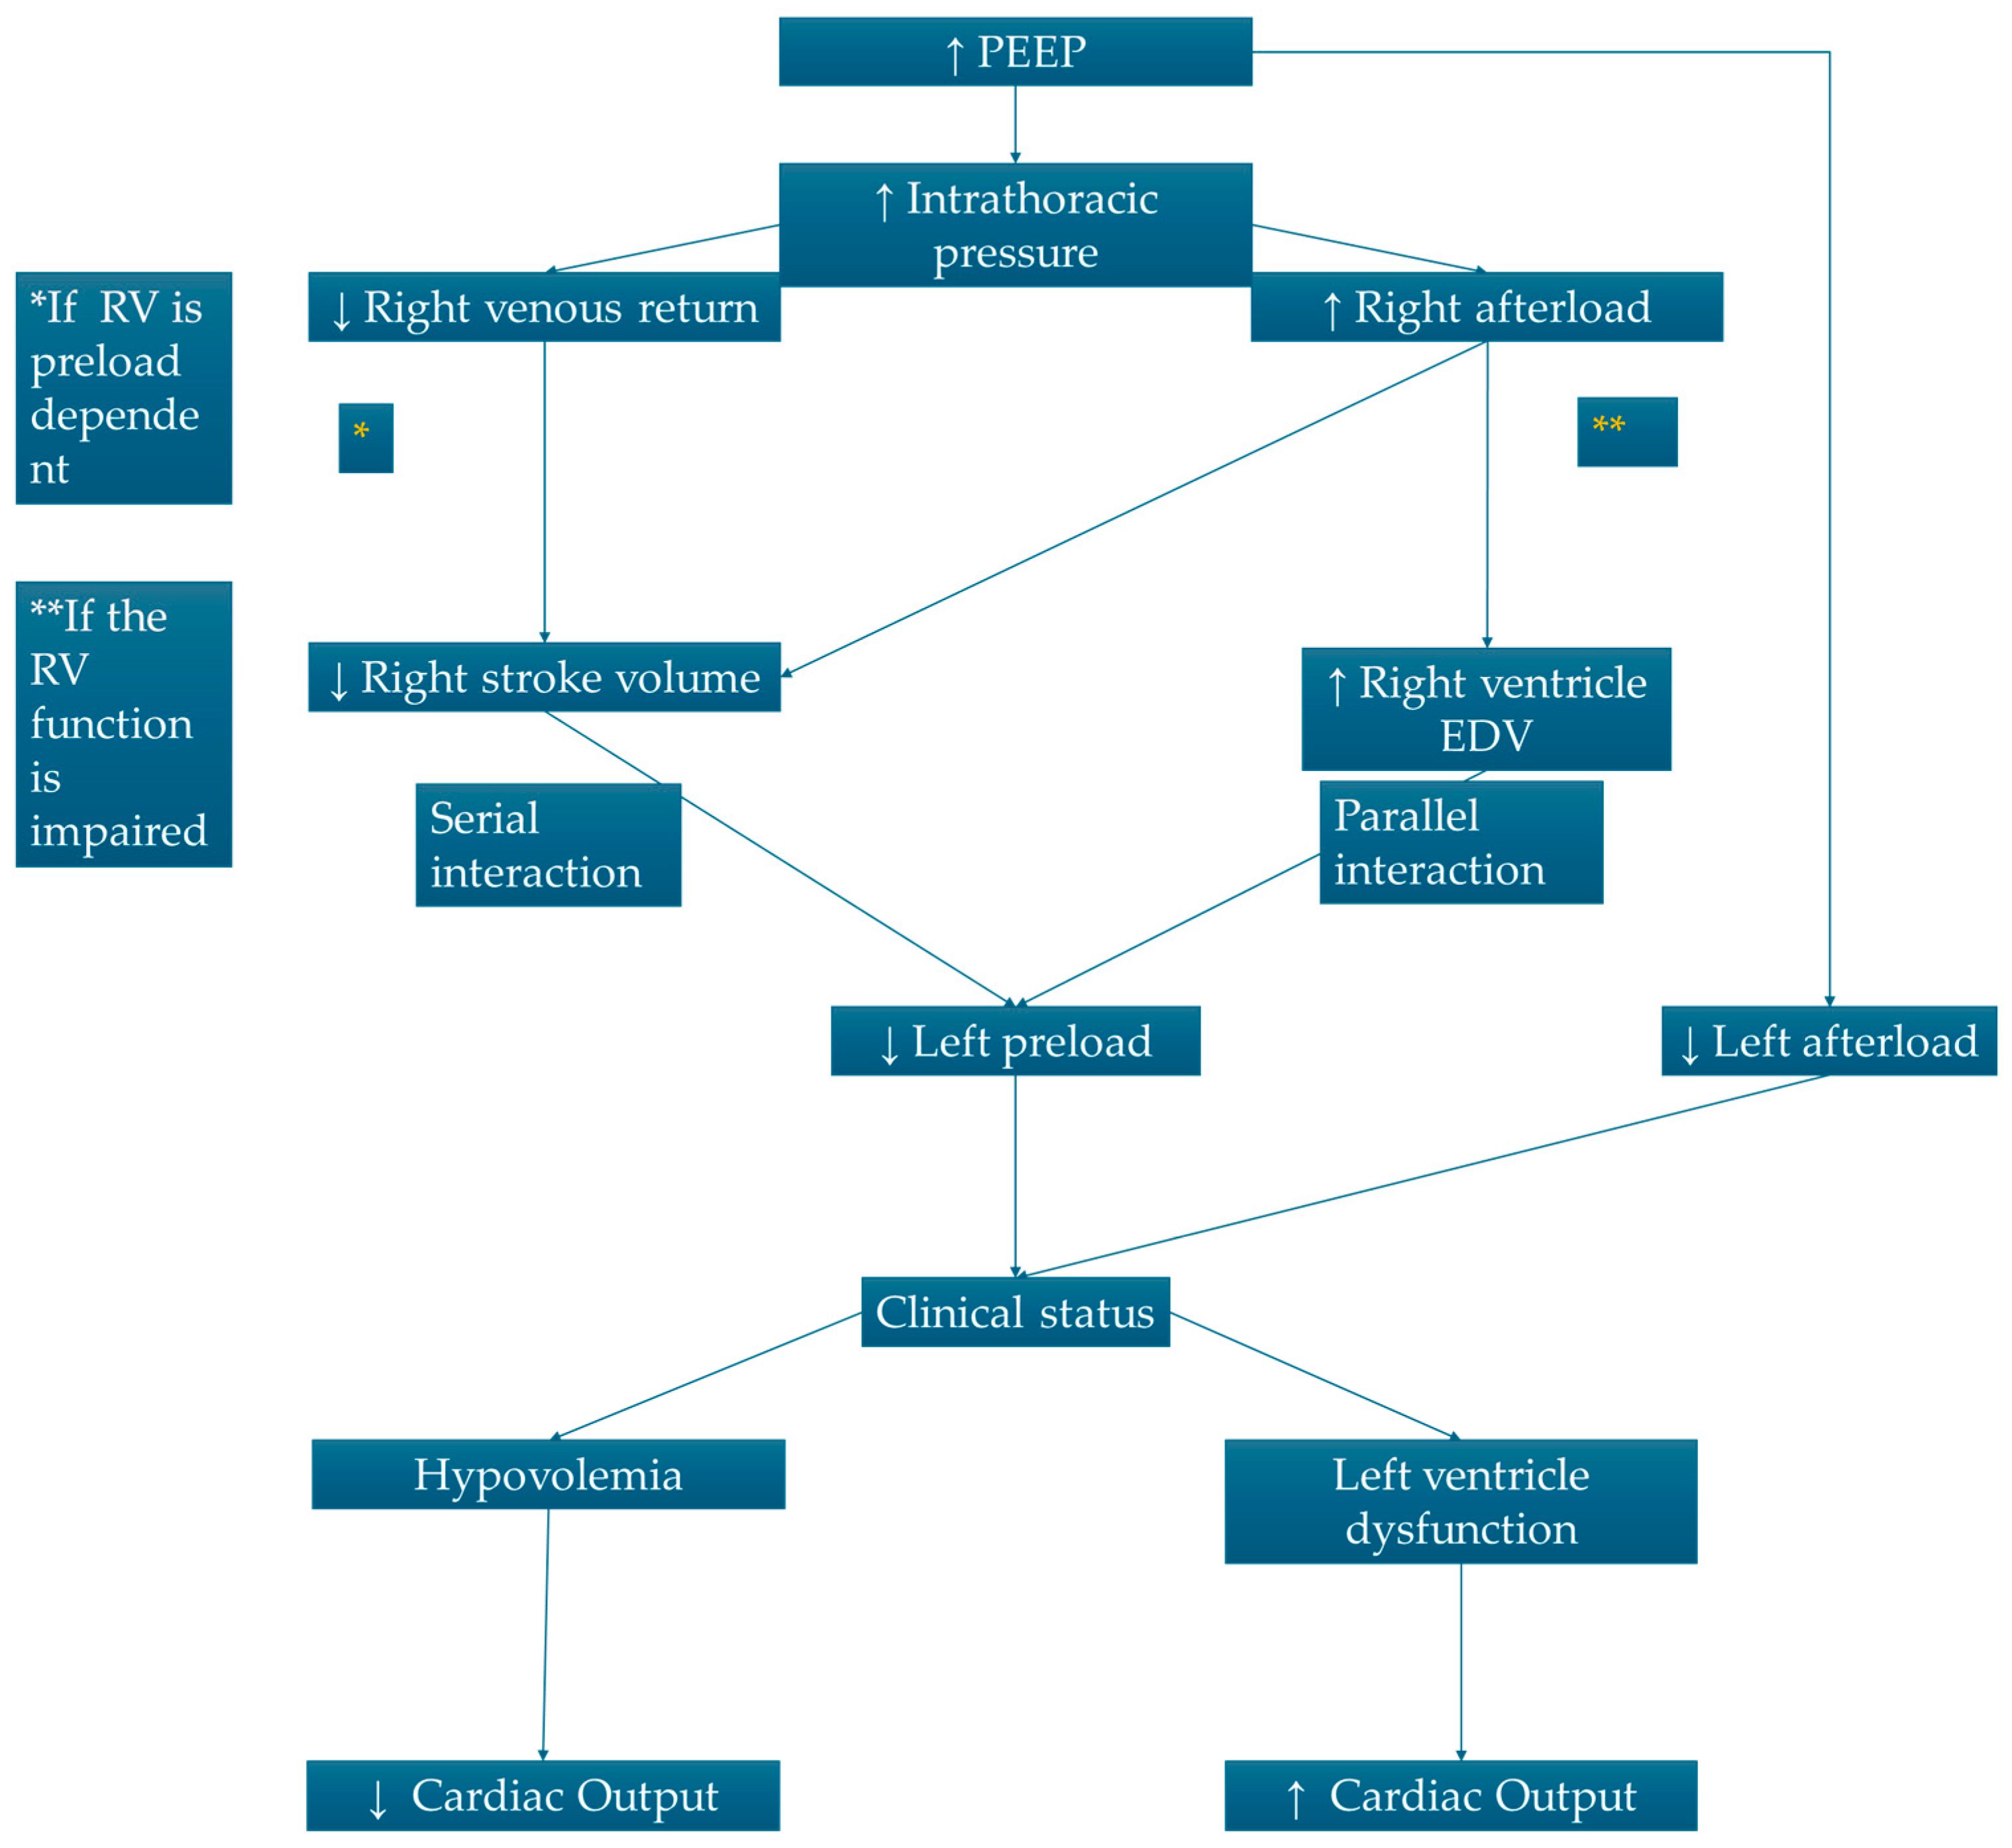

3. Heart–Lung Interaction in Mechanical Ventilation